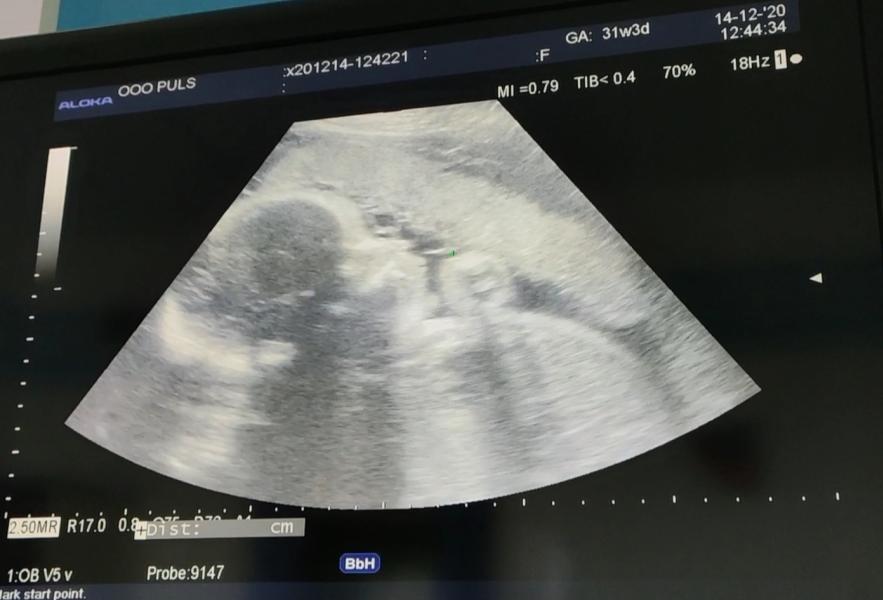

Божечки. Узи показало, что он уже 3200 😱 чтож дальше будет?) Еще ходить и ходить....